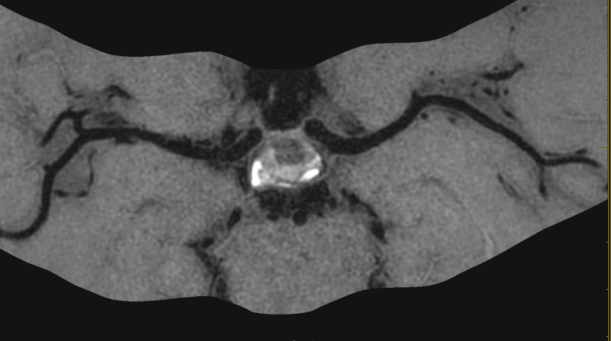

3招丨找出壁间血肿(动脉夹层)

ef67d9fa36dc94c9d4ac5fd611a15201.png

1 TOF-MRA图可见颈内动脉内膜片影

2 CE-MRA图可见颈内动脉真假腔显示

266bdc3b78e99e1e45b42d871817ee31.png

13D-T1-SPC图显示打药前颈内动脉C1C2段高亮的壁间血肿及管腔重度狭窄。

23D-T1-SPC图显示打药后血肿及相应节段血管壁都强化不明显。